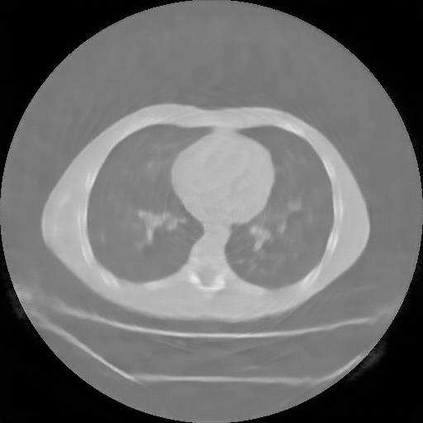

Sparse-view computed tomography (CT) is known as a widely used approach to reduce radiation dose while accelerating imaging through lowered projection views and correlated calculations. However, its severe imaging noise and streaking artifacts turn out to be a major issue in the low dose protocol. In this paper, we propose a dual-domain deep learning-based method that breaks through the limitations of currently prevailing algorithms that merely process single image slices. Since the scanned object usually contains a high degree of spatial continuity, the obtained consecutive imaging slices embody rich information that is largely unexplored. Therefore, we establish a cascade model named LS-AAE which aims to tackle the above problem. In addition, in order to adapt to the social trend of lightweight medical care, our model adopts the inverted residual with linear bottleneck in the module design to make it mobile and lightweight (reduce model parameters to one-eighth of its original) without sacrificing its performance. In our experiments, sparse sampling is conducted at intervals of 4{\deg}, 8{\deg} and 16{\deg}, which appears to be a challenging sparsity that few scholars have attempted before. Nevertheless, our method still exhibits its robustness and achieves the state-of-the-art performance by reaching the PSNR of 40.305 and the SSIM of 0.948, while ensuring high model mobility. Particularly, it still exceeds other current methods when the sampling rate is one-fourth of them, thereby demonstrating its remarkable superiority.